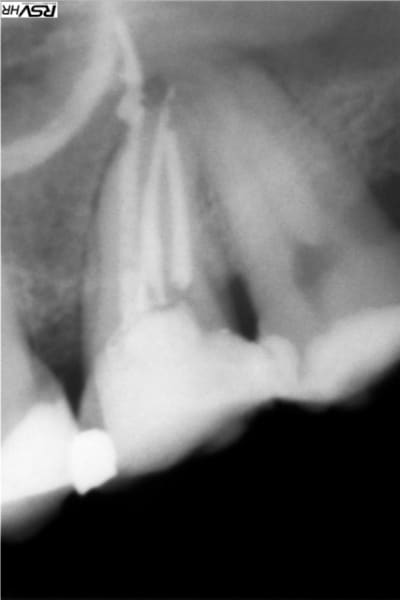

Il n'y a pas que la technique d'obturation qu'il faut revoir mais aussi l'alésage. Sur la radio, l'apex est défoncé: la racine à une courbure mésiale et l'obturation est rectiligne et perfore la racine à la courbure apicale.

La pâte est partie droite dans l'os (qui a dû être aussi alésé ...) et a fusé en nappe quand elle a atteint le sinus.

En plus c'est sur-alésé et certainement avec des instruments trop rigides qui ont tout défoncé.

ci-joint un cas de dépassement de pâte canalaire après compactage mac spadden

heureusement pour moi et le patient la pâte du sealite regular

s'est dissous naturellement de fin 2012 (dépassement)

à fin 2015 trace disparue

Je te donne mon interprétation "airylis"

tu as une 14 avec 2 racines la palatine plus longue qui donne donc l'impression d’être devant la racine vestibulaire

le cône de gutta ne suit pas la courbure donc alésage légèrement droit et faux canal et donc la pâte a fusé

et suivi la courbure de ton sinus d’où l'arc de cercle;

la membrane de schneider a sans doute empêché la pâte de fuser dans le sinus;donc pour moi pas d'effraction de la membrane sinusienne sion image verticale....

Oui la pate ne semble pas être dans le sinus mais entre la membrane et l'os , mais d'une part je mets très peu de pate et d'autre part cette image ne ressemble pas à un dépassement , c'est "canalisé" ... J'arrive maintenant à positiver car le scanner du sinus fait quelques jours apres révèle plusieurs anomalies mais ne parle pas de ma pate et le patient est content de ne plus avoir ses douleurs sinusales , mais j'ai mis plusieurs jours à retrouver le sommeil aprés ce traitement et à oser faire des endos ...

Je pense que tu as fait ce qu'on appelle un zipping de ton apex. en gros tes limes de mise en forme ont peu à peu dévier la courbure. En gros apex explosé...

Tu as sûrement fait une erreur de calibration de ton maître cône de gutta. Toujours vérifier qu'on aune bonne butée. Il semble que ton dépassement soit un mélange de gutta et de pâte, donc peu probable que cela se résorbe.

Même chose que M2, faux canal avec dépassement (ne suit pas la courbure apicale) et fusée de pâte. On le voit bien sur la radio